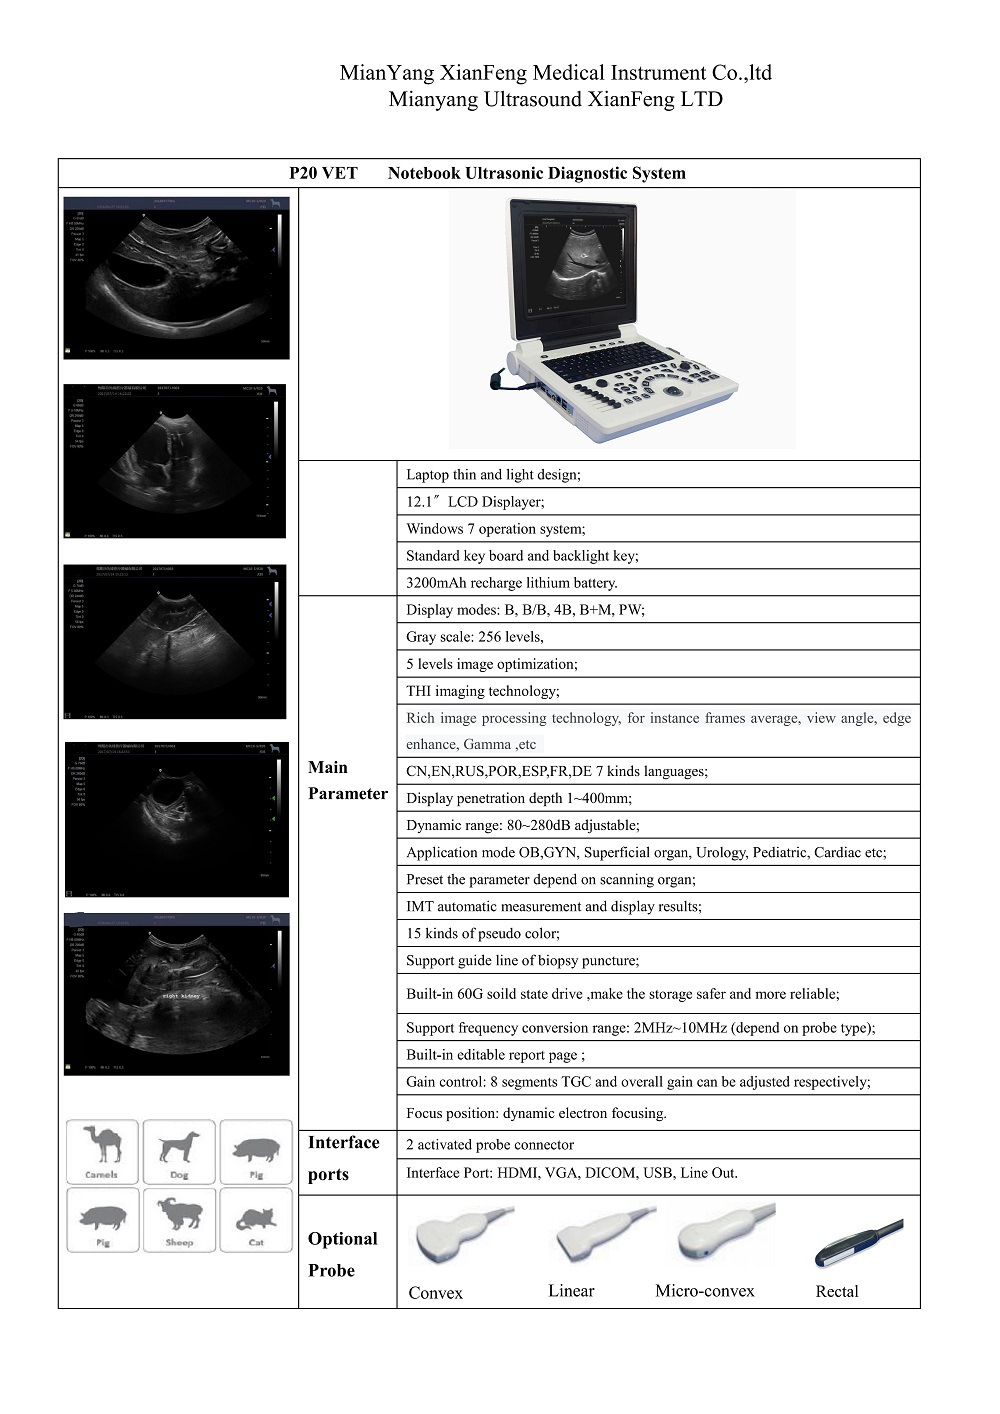

Портативный ультразвуковой аппарат Animal B; Выпуклый массивный зонд; Линейный зонд; Слегка выпуклый зонд; ректальный зонд